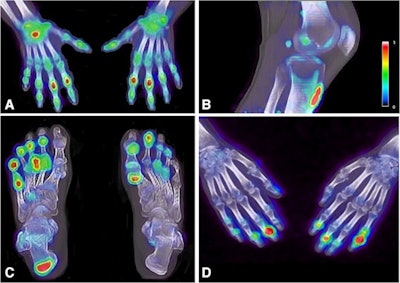

F-18 sodium fluoride (NaF) PET/CT may be a valuable tool for imaging patients with psoriatic arthritis (PsA), as it reveals new bone formation in peripheral joints missed on clinical evaluation, according to a Dutch group.

In this study, the researchers enrolled 16 patients with a clinical diagnosis of psoriatic arthritis from a rheumatology center at Amsterdam UMC. Patients underwent whole-body PET/CT scans 45 minutes after injection with F-18 NaF, a radiotracer that can identify new bone formation based on osteoblastic activity.